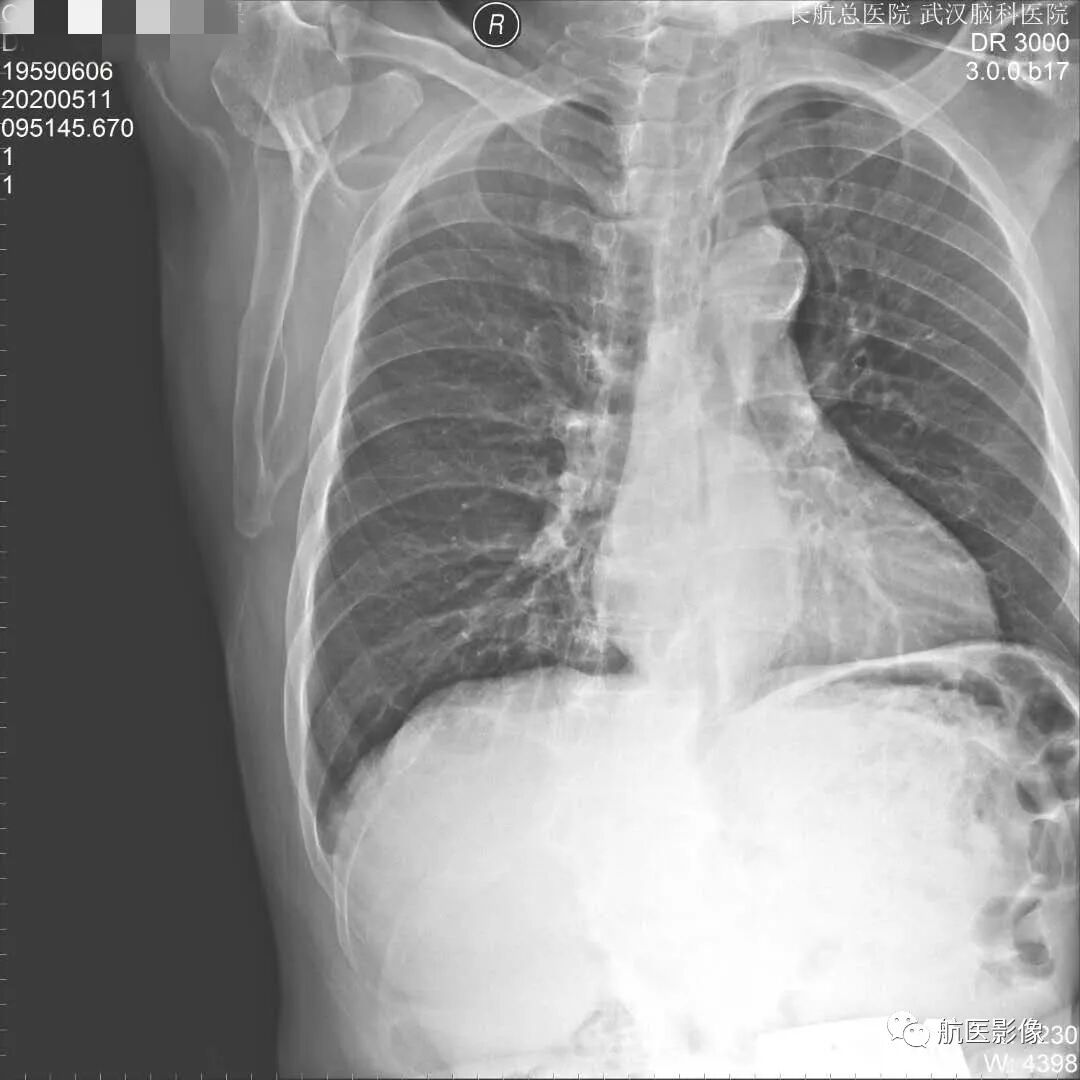

因此多层螺旋CT扫描及三维重建成像在诊断肋骨骨折方面比胸片具有明显优势,特别是靠近胸椎的胸肋关节处及无明显移位的骨折。请注意大多数肋骨骨折的原因是车祸及意外事故,其中很多都涉及到司法鉴定,能够准确诊断肋骨骨折及合并症就显得格外重要。对于急诊的胸部外伤,特别是复合伤患者,多层螺旋CT扫描及三维重建成像,能在极短时间内一次扫描完成,准确诊断肋骨骨折及合并症,可避免胸片检查中需变换体位而造成病情加重,为临床治疗赢得宝贵时间,同时也避免不必要的医疗纠纷。对于胸片怀疑骨折、涉及纠纷且胸片未见明确骨折、胸部外伤临床症状重者均需做多层螺旋CT扫描及三维重建成像,这能为患者提供准确的诊断及治疗,并保护患者的合法权利。

多层螺旋CT扫描及三维重建成像能快速、准确地显示肋骨骨折及合并症,不仅大大减少骨折的误诊、漏诊,还可以为司法鉴定提供更加准确、可靠的客观资料;多层螺旋CT扫描及三维重建成像技术组合对肋骨骨折的诊断较常规的胸片提供更加丰富的影像信息,能显示肋骨骨折位置、形态、数量及合并症,在对肋骨骨折诊断中具有不可替代的优势。